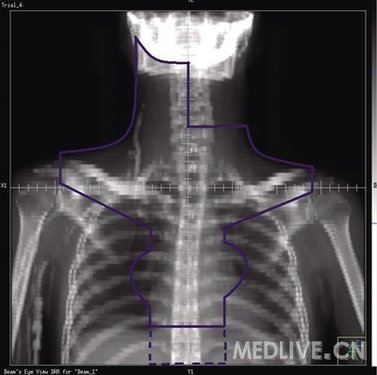

淋巴瘤放疗范围:受累野还是扩大野?

Ⅰ~Ⅱ期淋巴瘤患者在经过合理治疗后,绝大多数可以长期存活。近年来,对Ⅰ~Ⅱ期淋巴瘤研究的重点之一是在不降低生存率的前提下,如何减少治疗引起的并发症。就放疗本身而言,其并发症主要与范围和剂量大小有关。

在关于放疗范围的研究中,对于早期霍奇金淋巴瘤(HL),在其接受综合治疗的情况下,目前共有4项随机分组研究比较了在相同化疗方案和化疗周期的前提下,采用传统的扩大野照射与缩小的受累野照射的疗效。结果显示,两组间无论是无进展生存(PFS)率还是总生存(OS)率都相同,但受累野照射组的急性副作用发生率显著低于扩大野照射组,不过,两组间长期并发症的差异还需要长期随访才能观察到。因此,对于早期HL,在综合治疗的前提下,放疗采用受累野就足够了,不需要再给予扩大野照射。

对于Ⅰ~Ⅱ期非霍奇金淋巴瘤(NHL),其化疗后也多接受受累野照射,原发结内NHL受累野照射的定义与HL相同。

受累野的定义

受累野并非简单的受累局部照射,每个受累野都有其明确的定义,现将采用常规放疗的情况下,常用受累野的定义描述如下。

注:目前三维适形放疗和调强放疗技术已广泛应用于淋巴瘤的治疗,其靶区定义参照下述范围、包括相应的淋巴结区域即可。